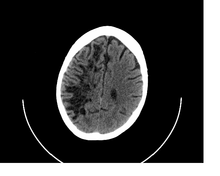

A perivascular space as seen on CT

CT image showing extensive low attenuation in the right hemispheric white matter due to dilated Type 2 perivascular spaces. This might be mistaken for vasogenic edema